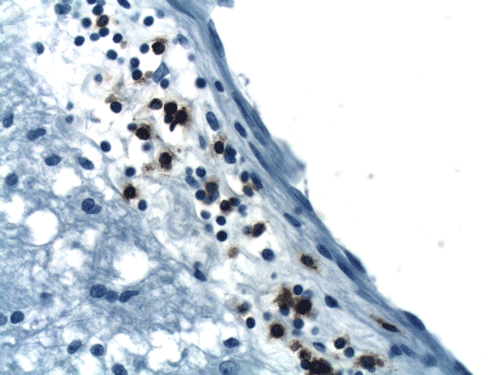

A left frontal lobe biopsy was performed and yield the following representative photomicrographs.

CD68

Q.

On CT scan, there is multiple hypodense white matter lesions that appear to spare a thin layer of subventricular white matter (Panel A). The T2-weighted images on MRI provides a more accurate estimation. The white matter in the occipital lobes is most affected (Panel A). There is extensive vacuolar changes in the white matter (Panel B and C) and there is a questionable increase in cellularity. In some of the thin walled blood vessels, there is a thin layer of perivascular lymphocytic infiltration which is free of atypia (Panel D, E, and F). The lymphocytes do not appear to extends into the parenchyma. On higher magnification, some large reactive astrocytes can be seen (Panel G). In a minority of areas, some concentric rings can be seen on hematoxylin-eosin stained sections (Panel H). These rings appear to be alternating rings of myelinated and demyelinated white matter and the vacuolar changes appear to be limited mainly to the concentric lesions. The adjacent myelinated areas are spared (Panel I). In some areas, the level of myelin loss appears to be proportional to the level of vacuolar changes (Panel J and K). On immunohistochemistry for glial fibrillary acidic protein (GFAP), the degree of gliosis is also more impressive in areas with more prominent vacuolar changes (Panel L and M). The vacuolar areas also appear to have a reduced density of axons (Panel N). Axonal spheroids are also present in these areas (Panel O). Although a prominent infiltration of foamy histiocytes is not noted on hematoxylin-eosin stains, immunohistochemistry for CD68 illustrated positive cells in a minority of demyelinated areas (Panel P). These cells lacks the foamy nature of macrophages and their morphology would suggest microglial cells. The reactive astrocytes are not immunoreactive for CD68 (Panel Q). Immunohistochemistry for T-cells (CD3) and B-cells (CD20) demonstrates only a thin rim of perivascular infiltration without significant extension into the surrounding parenchyma (Panel R, S, and T).